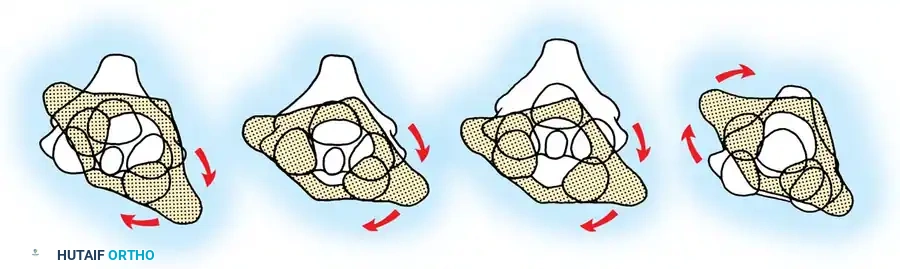

Fig 2. Diagrammatic representation of facet subluxation and dislocation mechanics.

Distractive Flexion (Four Stages)

Characterized by an axis of flexion anterior to the vertebral body, placing the posterior elements under extreme tension.

* Stage 1: Failure of the PLC, evidenced by facet subluxation in flexion and abnormal divergence of the spinous processes (widened interspinous distance).

* Stage 2: Unilateral facet dislocation. Subluxation of the contralateral facet suggests severe ligamentous injury. Beatson's serial sectioning studies demonstrated that unilateral dislocation can occur with rupture of only the posterior interspinous ligament and the facet capsule.

* Stage 3: Bilateral facet dislocations, presenting with approximately 50% anterior subluxation of the vertebral body. This requires complete rupture of the interspinous ligament, both facet capsules, the posterior longitudinal ligament (PLL), and the annulus fibrosus.

* Stage 4: Full vertebral body width displacement anteriorly. This creates a grossly unstable motion segment, often termed a "floating" vertebra.